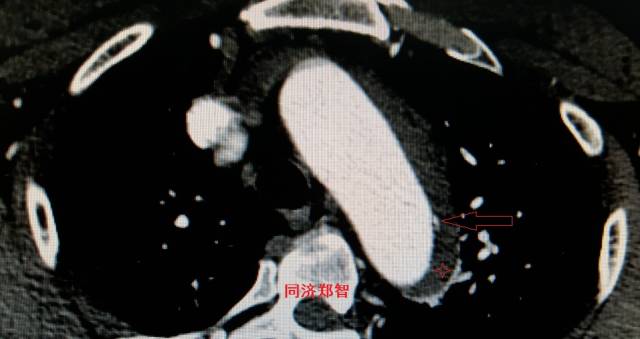

病例十一

平扫CT发现主动脉血管内孤立的钙化点(红色箭头所示),CTA证实为降主动脉溃疡合并壁间血肿。